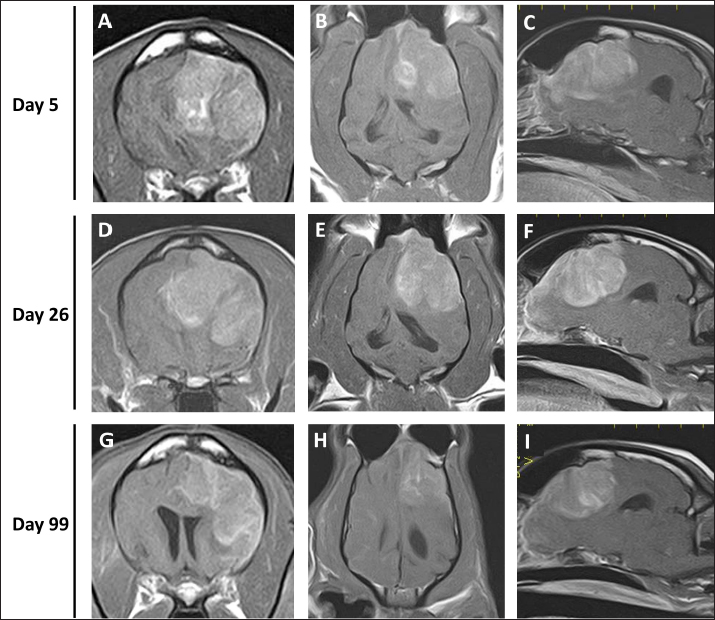

As intracranial disease was suspected in the present case, magnetic resonance imaging (MRI) using a 1.5 Tesla superconducting unit (Vantage Elan, Canon Medical Systems, Otawara, Japan) was performed as further investigation on day 5. MRI revealed a solid mass in the left frontal lobe that the lesion was 32.4 × 29.9 × 27.7 (length × width × height) mm in size showing homogeneous contrast enhancement that shifted the brain midline to the right in contrast enhancement T1-weighted image (T1WI) (Fig. 1A–C). Continuity with the meninges was observed at the tumor margin on contrast-enhanced T1WI. High-signal intensity findings in the brain parenchyma around the tumor indicate edema and/or inflammation on T2-weighted imaging (T2WI) and fluid-attenuated inversion recovery (FLAIR) images. Cerebrospinal fluid was not collected because increased intracranial pressure was suspected based on the MRI findings of transtentorial herniation. MRI findings indicated the possibility of meningioma or HS, and the owner requested surgical volume reduction and medical treatment with anticancer drugs. Radiotherapy was refused because of the cost, and prednisolone (PREDONINE tablets 5 mg; Shionogi & Co, Osaka, Japan) was prescribed at 1 mg/kg once a day until the operation. On day 26, an MRI examination was performed again, revealing that the lesion had grown to 34.7 × 29.9 × 34.9 mm (Fig. 1D–F). The next day, a surgical biopsy due to transfrontal craniotomy was performed to reduce intracranial pressure and confirm the diagnosis. The dog was premedicated with maropitant (1 mg/kg; Cerenia, Zoetis Japan, Tokyo, Japan), fentanyl (3 μg/kg; Fentanyl Injection 0.5 mg, Terumo Corporation, Tokyo, Japan), and lidocaine (2 mg/kg; Lidocaine Intravenous Injection 2%, Terumo corporation), all administered intravenously (IV). General anesthesia was induced with propofol (Propofol Intravenous Injection 1%, Maruishi Pharmaceutical, Osaka, Japan) to facilitate IV until intubation could be performed, following which propofol-based total intravenous anesthesia accompanied by constant rate infusions of fentanyl (10 to 15 μg/kg/hr) and medetomidine (1 to 3 μg/kg/hr; Dorbene, Kyoritsu Seiyaku Corporation, Tokyo, Japan) was administered to maintain anesthesia. Methylprednisolone sodium succinate (10 mg/kg; Solu-Medrol, Pfizer Japan, Tokyo, Japan) and fructose-supplemented glycerol (GLYCEOL for I.V. Infusion, TAIYO Pharma, Tokyo, Japan) were administered IV for 30 minutes to ensure neuroprotection and intracranial pressure reduction, respectively, during the intraoperative period. Although the tumor was visible on craniotomy, it bled easily, and only a small amount of tissue was collected. MRI was performed after surgery, but no significant changes were observed in the size of the tumor (Fig. 2). After the procedures, the patient was allowed to recover from anesthesia and emerged uneventfully 1 hour after extubation. Postoperative management comprising a crystalloid fluid infusion, prednisolone (2 mg/kg once a day), and zonisamide (Epiless tablet, Kyoritsu Seiyaku Corporation, Tokyo, Japan) at 3 mg/kg twice daily was additionally prescribed.

Fig. 2. Postcontrast transverse (A) and dorsal (B) T1WI of the case on day 27. No major changes in the size of the contrastenhanced tumor after surgery were observed.

On day 99, the patient presented with acute onset of somnolence and recumbency. Cerebral infarction was suspected because the entire right cerebral hemisphere and part of the thalamus showed high signal intensity on T2WI and FLAIR images, high signal intensity on diffusion weighted Imaging (DWI) images, and equal signal intensity on the ADC map (Fig. 4). MRI at this time demonstrated that the HS lesion in the left frontal lobe was 28.1 × 24.3 × 22.2 cm in size and had clearly regressed (Fig. 1G–I). The patient was also prescribed rivaroxaban (0.25 mg/kg, twice a day; Xarelto tablets 10 mg; Bayer Yakuhin, Osaka, Japan), and the owners were instructed to perform follow-up at home. The patient's neurological symptoms gradually improved, and a third dose of ACNU was administered at 20 mg/m2 on day 110. However, on day 124, an MRI was performed because a neurological examination revealed a decrease or loss of facial sensation, and trigeminal nerve injury was suspected. Although a contrast agent could not be used because the procedure was performed without anesthesia, clear re-enlargement of the HS lesions was observed (Fig. 5). ACNU was therefore changed to temozolomide (Temozolomide Tablets 20 mg “NK,” Nippon Kayaku, Tokyo, Japan), which was administered at an oral dose of 120-140 mg/m2 once daily for 5 days over a 28-day cycle on day 131, 153, and 173. During this time, there were no major changes in the patient's clinical symptoms, and the patient was able to walk with some unsteadiness. However, the patient died suddenly on day 195. A pathological autopsy was not performed at the owner's request.

Fig. 4. MR images of the case at the level of thalamus on day 99. The entire right cerebral hemisphere and part of the thalamus showed a high signal on (A) T2-weighted and (B) FLAIR images, a high signal on (C) DWI images, and an equal signal on (D) ADC-map.